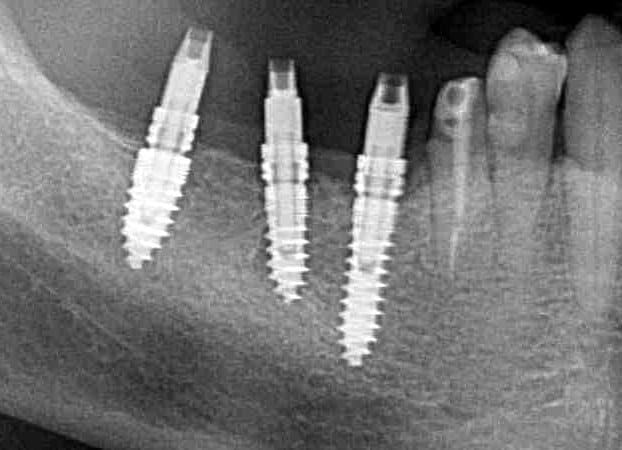

Pour ceux que ca interessent, et parce qu on a m a demandé des cas supplémentaires dans le sujet 23 implants rehabilitation totale, voici un autre cas d implantation immédiate avec la technique minimalement invasive et condensation grace aux forets.

Le patient a reçu un traitement il y a dix ans dans le maxillaire et dans le 4eme quadrant.Comme on peut le voir j´ai du extraire quelques dents au maxillaire: 35 37 et 45.

Le septum de la 37 a été foré avec un foret conique 3 faces.

J ai planté à 60 Ncm sans fracturer le septum.Juste après l opération , les prep caps en zircon ont été cémenté.La restauration définitive 34 jusqu` à 37 été fixé 2 semaines après l implantation avec implantlink (detax). Après un an, le bridge a été retiré facilement pour voir l´état de la gencive et faire une radio de contrôle.On la re ossifiction est satisfaisante et que la gencive "aime" le zircon.

Le bridge a ensuite été recémenté sans correction nécessaire du bridge.